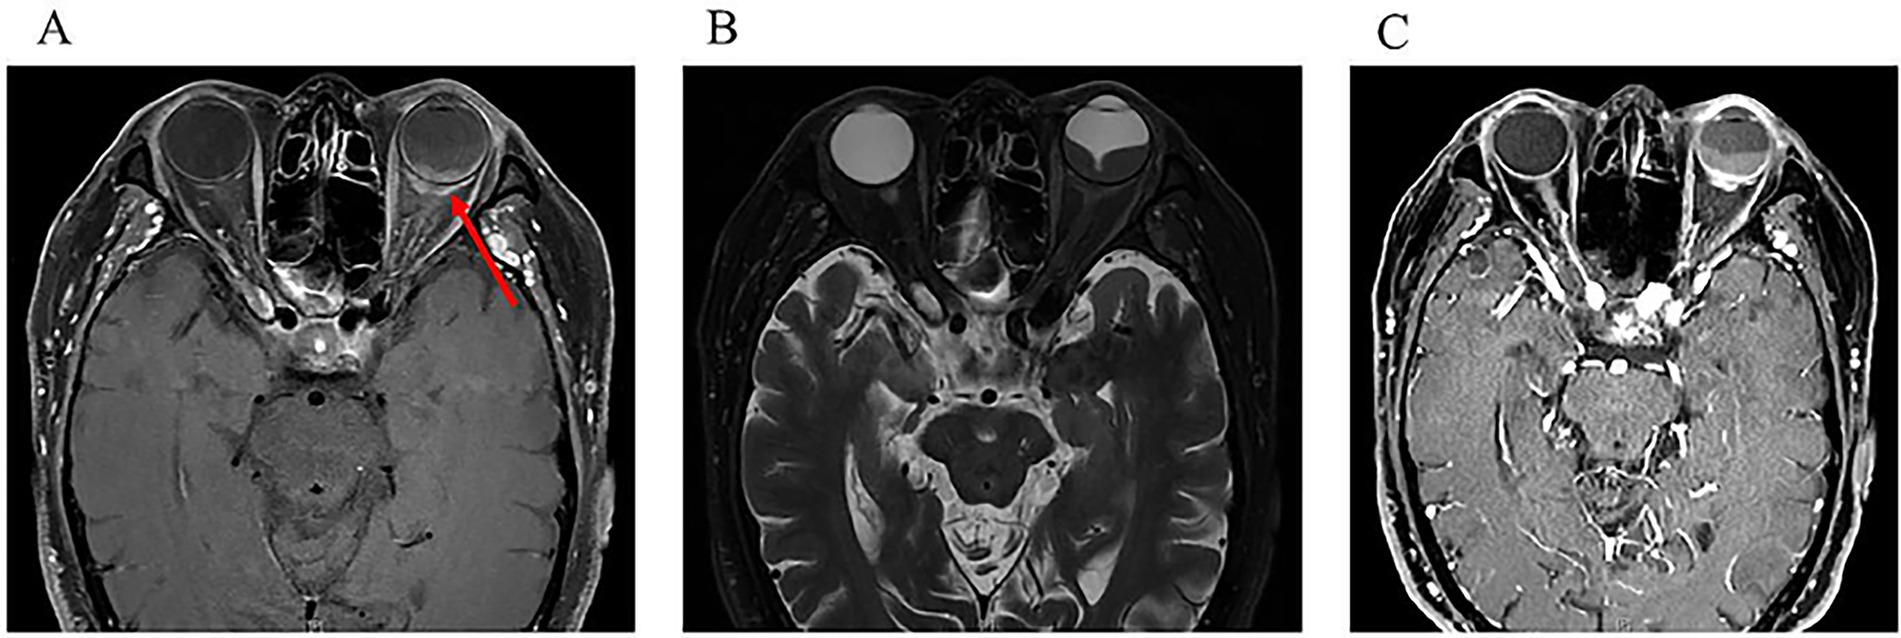

The patient was lost to follow up for 1 year and returned to our department in August 2022 due to the deterioration of visual acuity in his left eye. Fundoscopy revealed an inferior exudative retinal detachment in the left eye (Figure 3A). Ultrasonography showed significant enlargement of the diffuse choroidal low-reflectivity mass and retrobulbar hypoechoic areas (Figure 3B). Furthermore, OCT of the left eye showed dome-shaped choroidal thickening with retinal folds (Figure 3C). Magnetic resonance imaging (MRI) of the head and orbits demonstrated extensive choroidal thickening with a maximal height of 2.8 mm, along with fusiform soft tissue encasing the optic nerve that appeared isointense on both T1- and T2-weighted sequences and exhibited mild heterogeneous enhancement; notably, there was no evidence of adnexal or central nervous system (CNS) involvement (Figure 4). Tumor markers and immunohistochemistry tests yielded normal results, excluding malignancies and autoimmune diseases. Consequently, the patient was referred to respiratory and hematology departments for a visit. Repeat chest CT showed stability of the pulmonary nodule compared with the prior scan. Although lung biopsy was recommended by pulmonologist, the patient declined the procedure.

Figure 4

One year after initial presentation. An MRI scan of the orbits showed a mass (arrow) of irregular shape, predomi-nantly affecting the posterior parts of the eyeball, as well as transscleral extension. (A) Horizontal view of T1-weighted sequences; (B) Horizontal view of T2-weighted se-quences; (C) Horizontal view on contrast-enhanced in T1-weighted sequences.